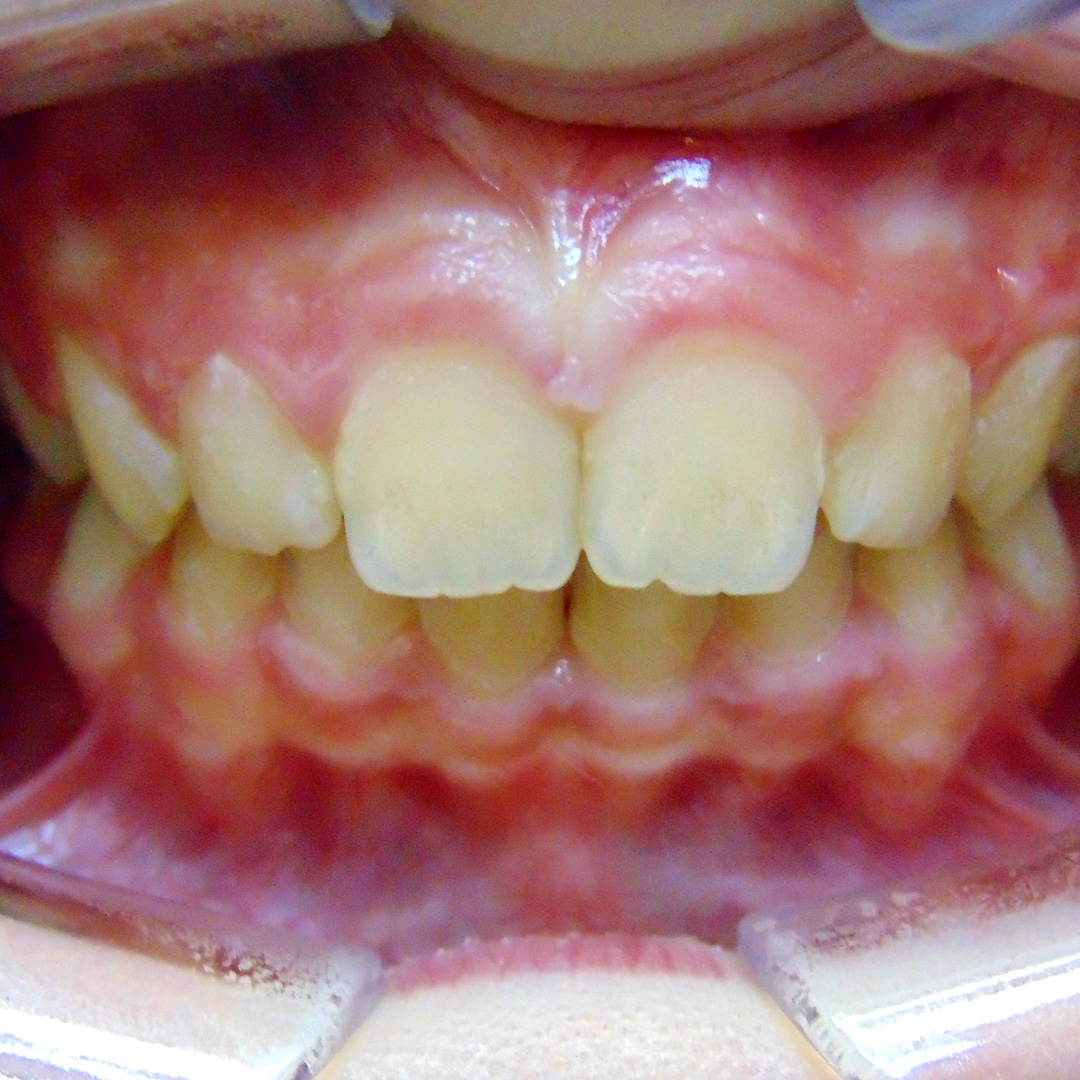

Родители пациента обратились в «Стоматологию Комфорта» для исправления неправильного прикуса у ребёнка 11-и лет. Врач-ортодонт Резниченко Анна Васильевна провела осмотр и установила, что у пациента наблюдается суперпозиция 23 зуба и вертикальная резцовая окклюзия. Врачом было принято решение о целесообразности лечения съёмным аппаратом-ортокорректором Occlus-o-Guide.

Ортокорректор Occlus-o-Guide производства США предотвращает нарушение окклюзии зубных рядов в сменном прикусе. Аппарат ускоряет процесс выравнивания зубных единиц у детей, а также способствует улучшению профиля ребёнка. Occlus-o-Guide предназначен для лечебных ортодонтических упражнений. Его применение направляет и смещает прорезывающиеся постоянные зубы к нормальной окклюзии.